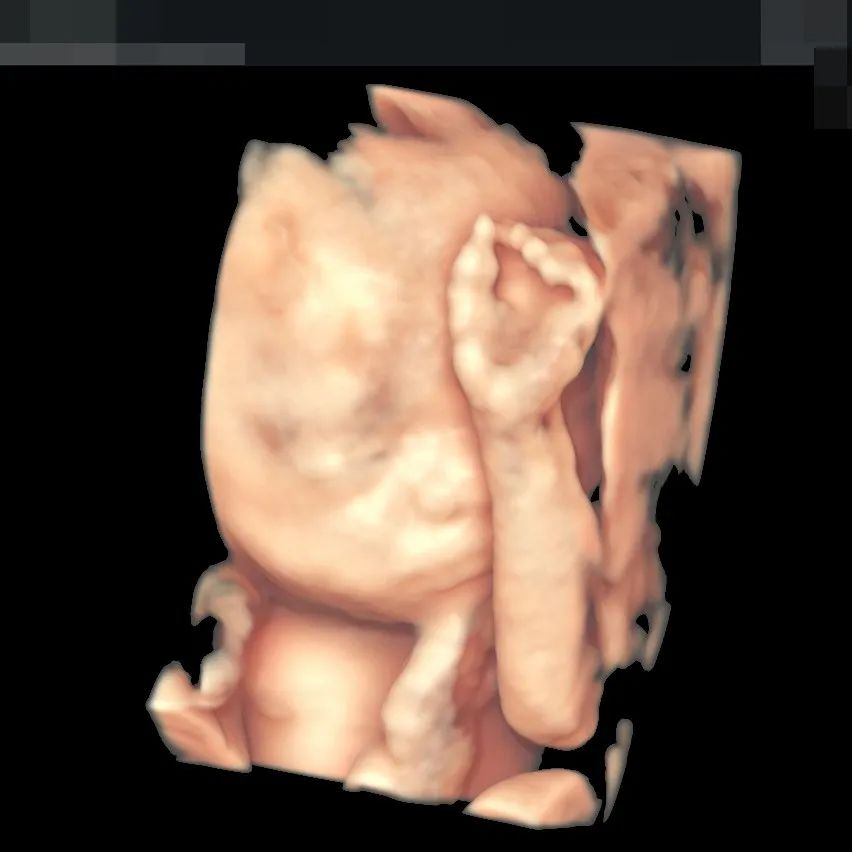

▲190斤孕妈王女士,不仅做了全面筛查,还留下了宝贵的胎儿影像,全家人都非常满意

超高清画质立体显示胎儿面部、脏器、四肢脊柱等发育情况,可高效筛查胎儿唇裂、骨骼发育异常以及中枢神经系统、呼吸系统、消化系统、泌尿系统、心脏的重大畸形。金标E10具备一整套胎心成像技术,支持从胎儿心脏结构到心功能的分析,可真实呈现胎心结构、脐带、血流变化,帮助临床医生及时作出诊断。“金标版”E10超真动态显示胎儿实时活动图像,画质全面颠覆传统视觉理念,堪比IMAX电影大片,让您看得更清晰、更直观。“金标版”GE-E10四维彩超,采用人体工程学设计,不存在射线、光波和电磁波等方面的辐射,对人体健康没有影响,孕妈妈们也可以安心检查。